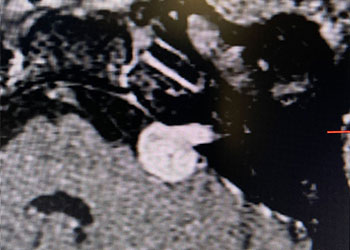

Brain:

74 Year Old Woman with Occipital Headaches

Author: Michael Brisman M.D., F.A.C.S., Read More!